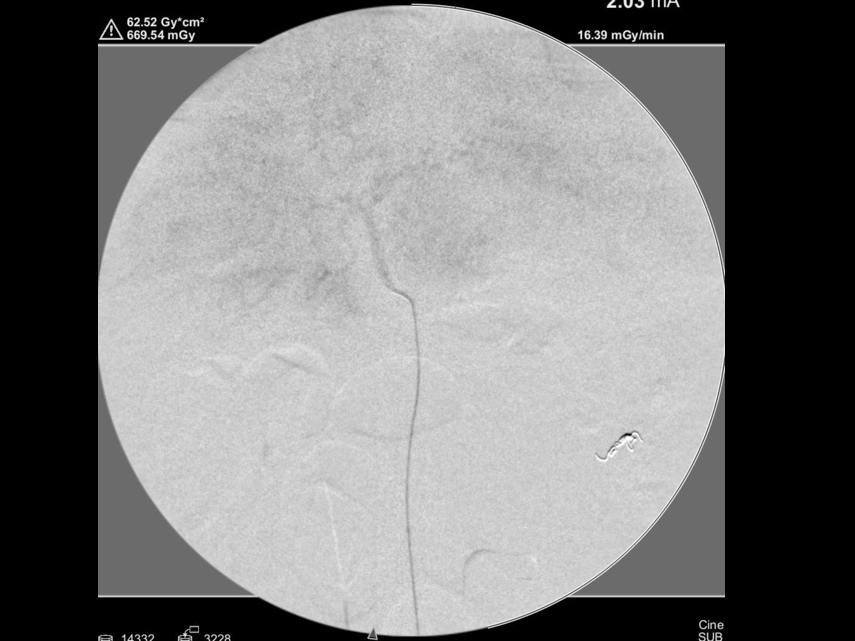

カテーテルを目的臓器まで挿入している様子